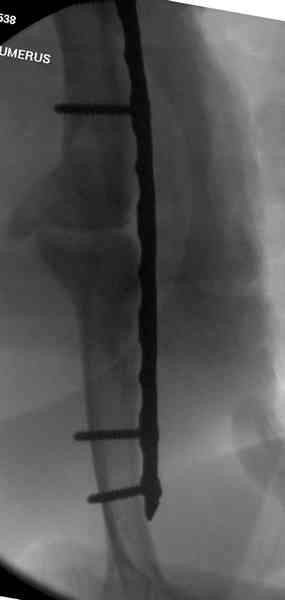

Как видно из выступлений коллег, способы фиксации

ложного сустава плеча могут быть различными, кто-то предпочитает аппаратом Илизарова (Соломин), пластинами (Волна) или интрамедуллярным гвоздем (Челноков).

Когда разбирался случай на сайте, и у нас была больная с похожей патологией, ложный сустав после поперечного перелома, леченного год назад где-то и кем-то в другом месте.

предложил Корнеев для лечения - применение анаболических стероидов - ретаболила, из-за его бессмысленности, также не согласились с его теорией, что любая операция заблокирует суставы, а наоборот, провели жесткую фиксацию пластиной для раннего восстановления.

Первичную пластину убрали недели 6 назад из переднего оригинального доступа, и из-за подозрительности тканей вокруг пластины, решили провести реконструкцию поэтапно.

Хотя сам не стороннник применения более массивных

имплантов для плеча, но для этого случая сделали

исключение. На снимке 4А диаметр мягких ткани около 20 см, при весе больной более 135 кг, и также выступление Андрея Волны подстегнуло к применению более массивной 4.5 мм локинг пластины.